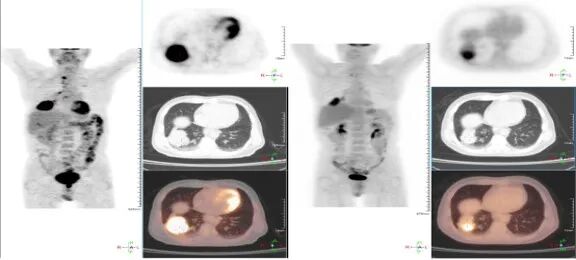

肺癌是发病率和死亡率增长最快 对人群健康和生命威胁最大的恶性肿瘤之一 换言之 发现得越早 治疗效果越好 我们与新华日报交汇点直播平台 江苏省科学传播中心合作 并邀请到了江苏省人民医院(南京医科大学第一附属医院)胸外科主任医师朱全 和我们聊一聊从肺结节到肺癌,如何实现精准诊疗? 专家简介 朱全,主任医师,江苏省人民医院胸外科副主任。中华医学会胸心血管外科学分会胸腔镜学组委员,中华医学会江苏省胸外科分会委员。 01 肺结节的性质 肺结节:< 3厘米 主要是指肺实质内单发或多发直径不超过 3 厘米 的圆形或类圆形结节影。不伴肺不张、肺钙化、肺门淋巴结肿大或胸膜渗出。 结节: <8毫米时称作亚厘米结节 <4毫米称作微结节 肿块: ≥ 3厘米 02 肺结节的分类 (1)实性结节 (2)半实性结节 (纯磨玻璃结节、混合磨玻璃结节) 实性结节 混合磨玻璃结节 结节分类 磨玻璃样结节 03 肺结节≠肺癌 •实性结节恶性率仅7% •部分实性结节恶性率为63% •纯磨玻璃结节恶性率为18% •>20 毫米的结节恶性率有80% 肺磨玻璃肺结节的演变 01胸部X光平片 对肺癌的漏诊率30% 不能发现肺小结节 02 薄层CT 5mm层厚已成为历史---导致误诊! 薄层CT比常规CT提供了7-10倍信息 (普通CT 60张对比 薄层CT 360-600张) 03 正确使用PET/CT • 能够评估结节的代谢活性。 • 对大于1厘米的实性结节有意义 • 对纯磨玻璃和混合性磨玻璃结节无效 • 不易区分炎症和结核 强调!!! 磨玻璃结节要经过随访 2-3个月的随访很重要 炎症的比例10% 随着时间会消失 肺结节CT影像AI辅助检测 外科手术的微创化 切口的微创化 全胸腔镜→3孔→2孔→单孔 肺切除范围的变化 非解剖性肺切除:楔形 解剖性肺切除:全肺切除、肺叶切除、肺段切除术、肺亚段切除术、肺次亚段切除术 肺段切除 早期肺癌的微创治疗外科手术的精准化 早期肺癌外科治疗中的规则: 保证肿瘤学效果是首要任务保留更多有功能的肺组织 三维CT支气管血管成像(3D-CTBA)肺结节与早期肺癌